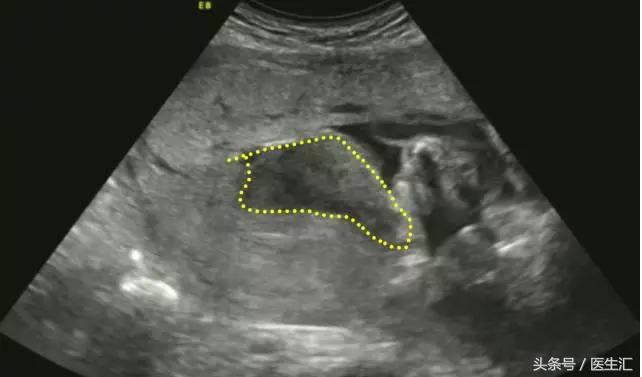

超声检查提示:宫底后壁胎盘与后壁肌层之间见混合回声区(超声表现1,见图1黄色圈内),与胎盘分界不清,范围约75mm×34mm,内回声不均匀,边缘及内部未见明显血流信号(检查要点1)。急诊剖宫产手术见胎盘80mm×50mm剥离面,占1/2(超过胎盘面积的1/3),宫腔积血约50ml,术后诊断胎盘早剥。

(图1)